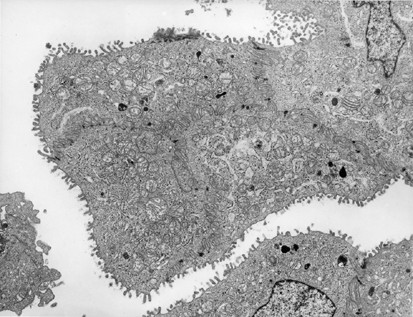

Figure 12 | Modern Pathology